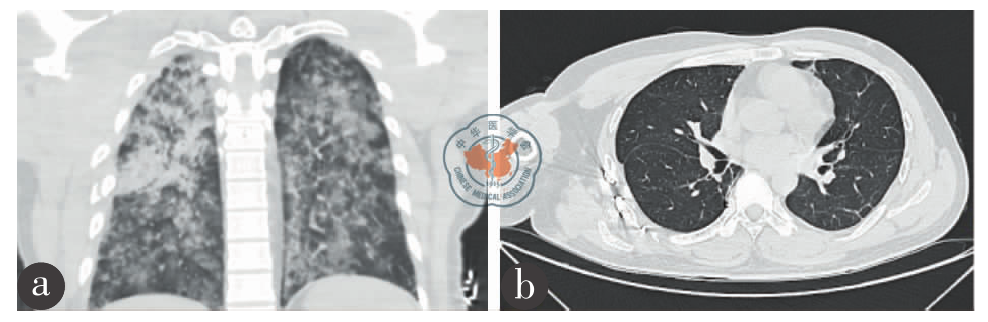

图1 FES并发ARDS及DAH患者胸部CT图